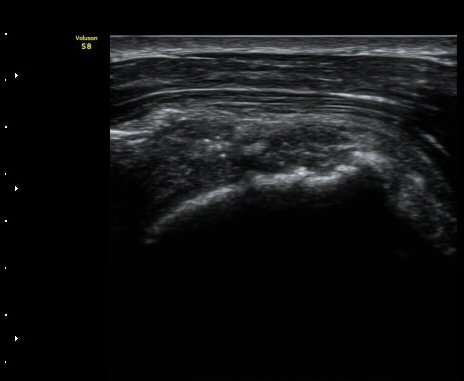

ÆÈÀ» ¿ÜȸÀüÇÏ´Ï °ß°©ÇÏ±Ù°Ç Ç¥ÃþÀÇ ¼ö¾×Àú·ù°¡ ´õ¿í È®½ÇÇÏ°Ô °üÂûµµ´Ï´Ù(»çÁø 4).